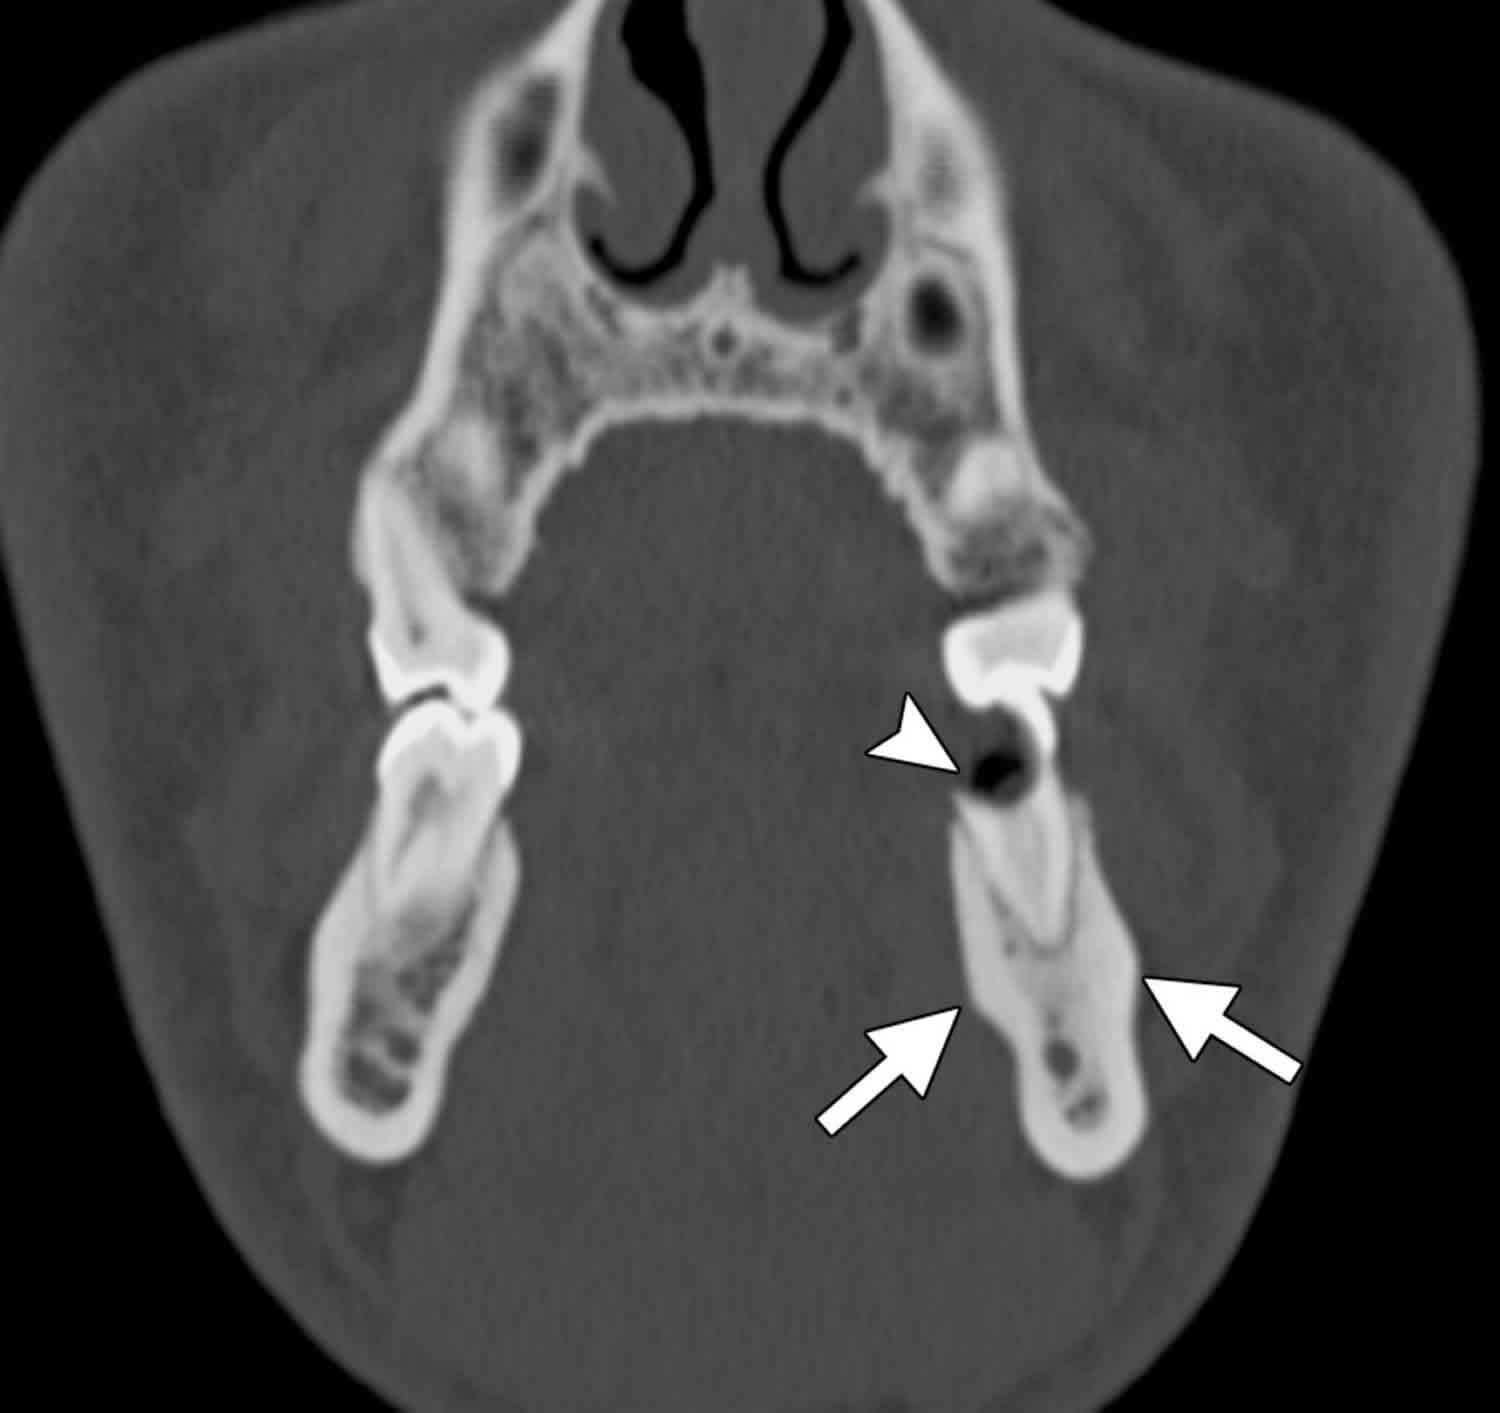

Figure 2 from Conservative Management of Condensing Osteitis of the Does Condensing Osteitis Need Treatment The treatment consists of surgical debridement and antibiotics to eliminate the infection and provide symptomatic relief. Condensing osteitis of the clavicle in children and adolescents should be recognized promptly. Condensing osteitis is a variant of chronic apical periodontitis and represents a diffuse increase in trabecular bone in response to irritation. Biopsy is needed to confirm diagnosis. When your dentist believes. Does Condensing Osteitis Need Treatment.